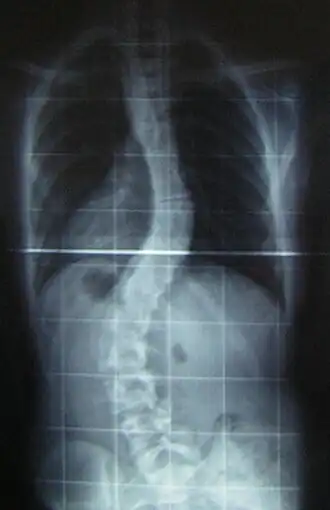

La scoliose est une déviation sinueuse de la colonne vertébrale dans les trois plans de l'espace : inclinaison dans le plan frontal, rotation des vertèbres dans le plan horizontal et inversion des courbures dans le plan sagittal. Il ne faut pas confondre la scoliose avec l'attitude scoliotique qui est une déviation dans un seul plan de l'espace, réductible et temporaire. La scoliose est une déformation permanente et irréductible. Une déviation du rachis est considérée comme une scoliose quand l'angulation est égale ou supérieure à 10 degrés.

Les clichés nécessaires sont une radiographie du rachis dorso-lombaire de face et de profil, fait chez un patient debout, avec compensation préalable d'une asymétrie de longueur des membres inférieurs[2].

Le principal critère d'évaluation de la scoliose est l'« angle de Cobb », qui se mesure sur une radiographie du rachis de face. C'est l'angle formé à partir de l'intersection de deux droites tangentielles l'une au plateau supérieur de la vertèbre limite supérieure, l'autre au plateau inférieur de la vertèbre limite inférieure. Les conventions médicales veulent qu'un angle inférieur à 10 degrés ne soit pas considéré comme une scoliose à part entière[35]. On peut classer les courbures scoliotiques en fonction de leur importance :